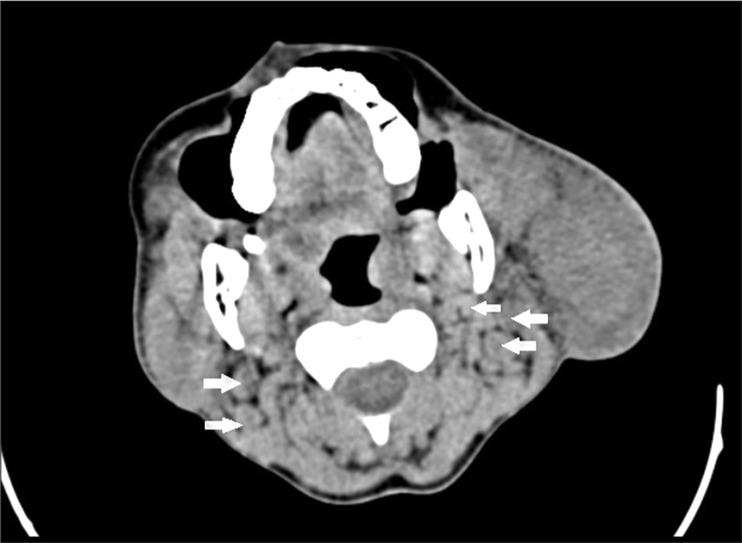

A middle-aged female patient presenting with a history of multiple chronic neck swellings was thoroughly evaluated by ultrasound (US), computed tomography (CT), and magnetic resonance imaging (MRI). The imaging findings included gross enlargement of the left parotid gland, a focal lesion in the right parotid gland, and cervical lymphadenopathy. These features correlated with histopathological findings, and the diagnosis of Kimura disease was made.

一名有多处慢性颈部肿胀病史的中年女性患者接受了超声(US)、计算机断层扫描(CT)和磁共振成像(MRI)的全面评估。影像学表现包括左侧腮腺明显肿大、右侧腮腺局灶性病变以及颈部淋巴结病。这些特征与组织病理学结果相关,从而做出了木村病的诊断。